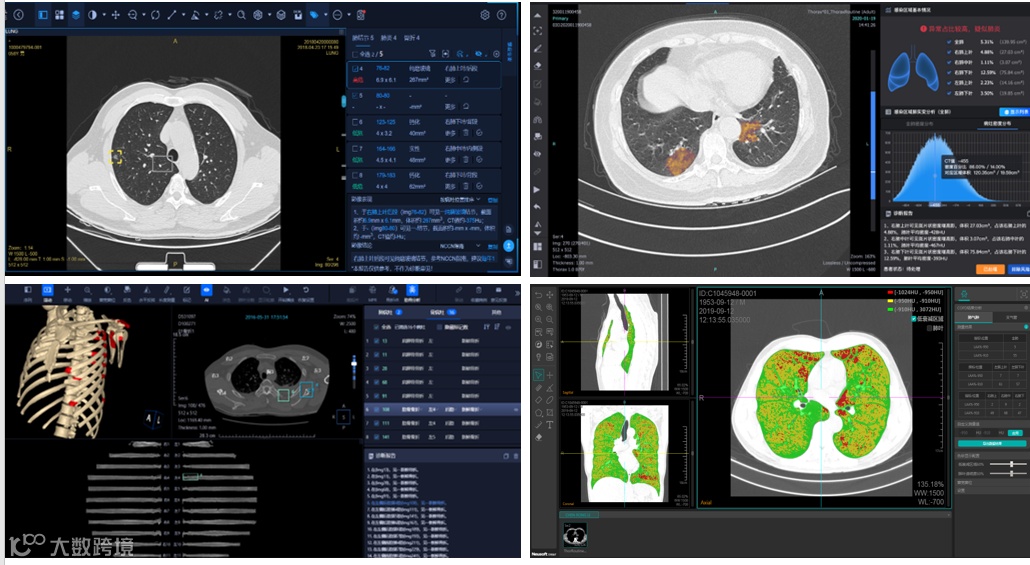

东软医疗基于多款人工智能辅助分析软件,打造出智慧胸AI解决方案,囊括了全胸、全肺健康。基于一次胸部CT平扫,不仅能实现肺癌的智能筛查,还可同时完成对慢阻肺、肺炎、胸部骨折等多种胸部疾病的智能检出,真正做到“一扫多查,一查多筛”。

智慧胸AI解决方案:肺结节AI、肺炎AI、骨折AI、慢阻肺筛查辅助软件

在肺癌智能筛查方面,东软医疗肺结节AI辅助分析软件能够自动、快速、不留遗漏地完成肺结节检出工作,并提供准确的性质分类、良恶性判断分析,大幅提升阅片与诊断准确率,让肺癌早筛更加精准高效。